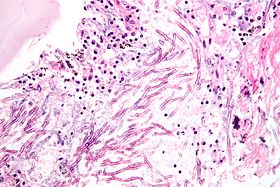

Fungi (aspergillus). H&E stain.